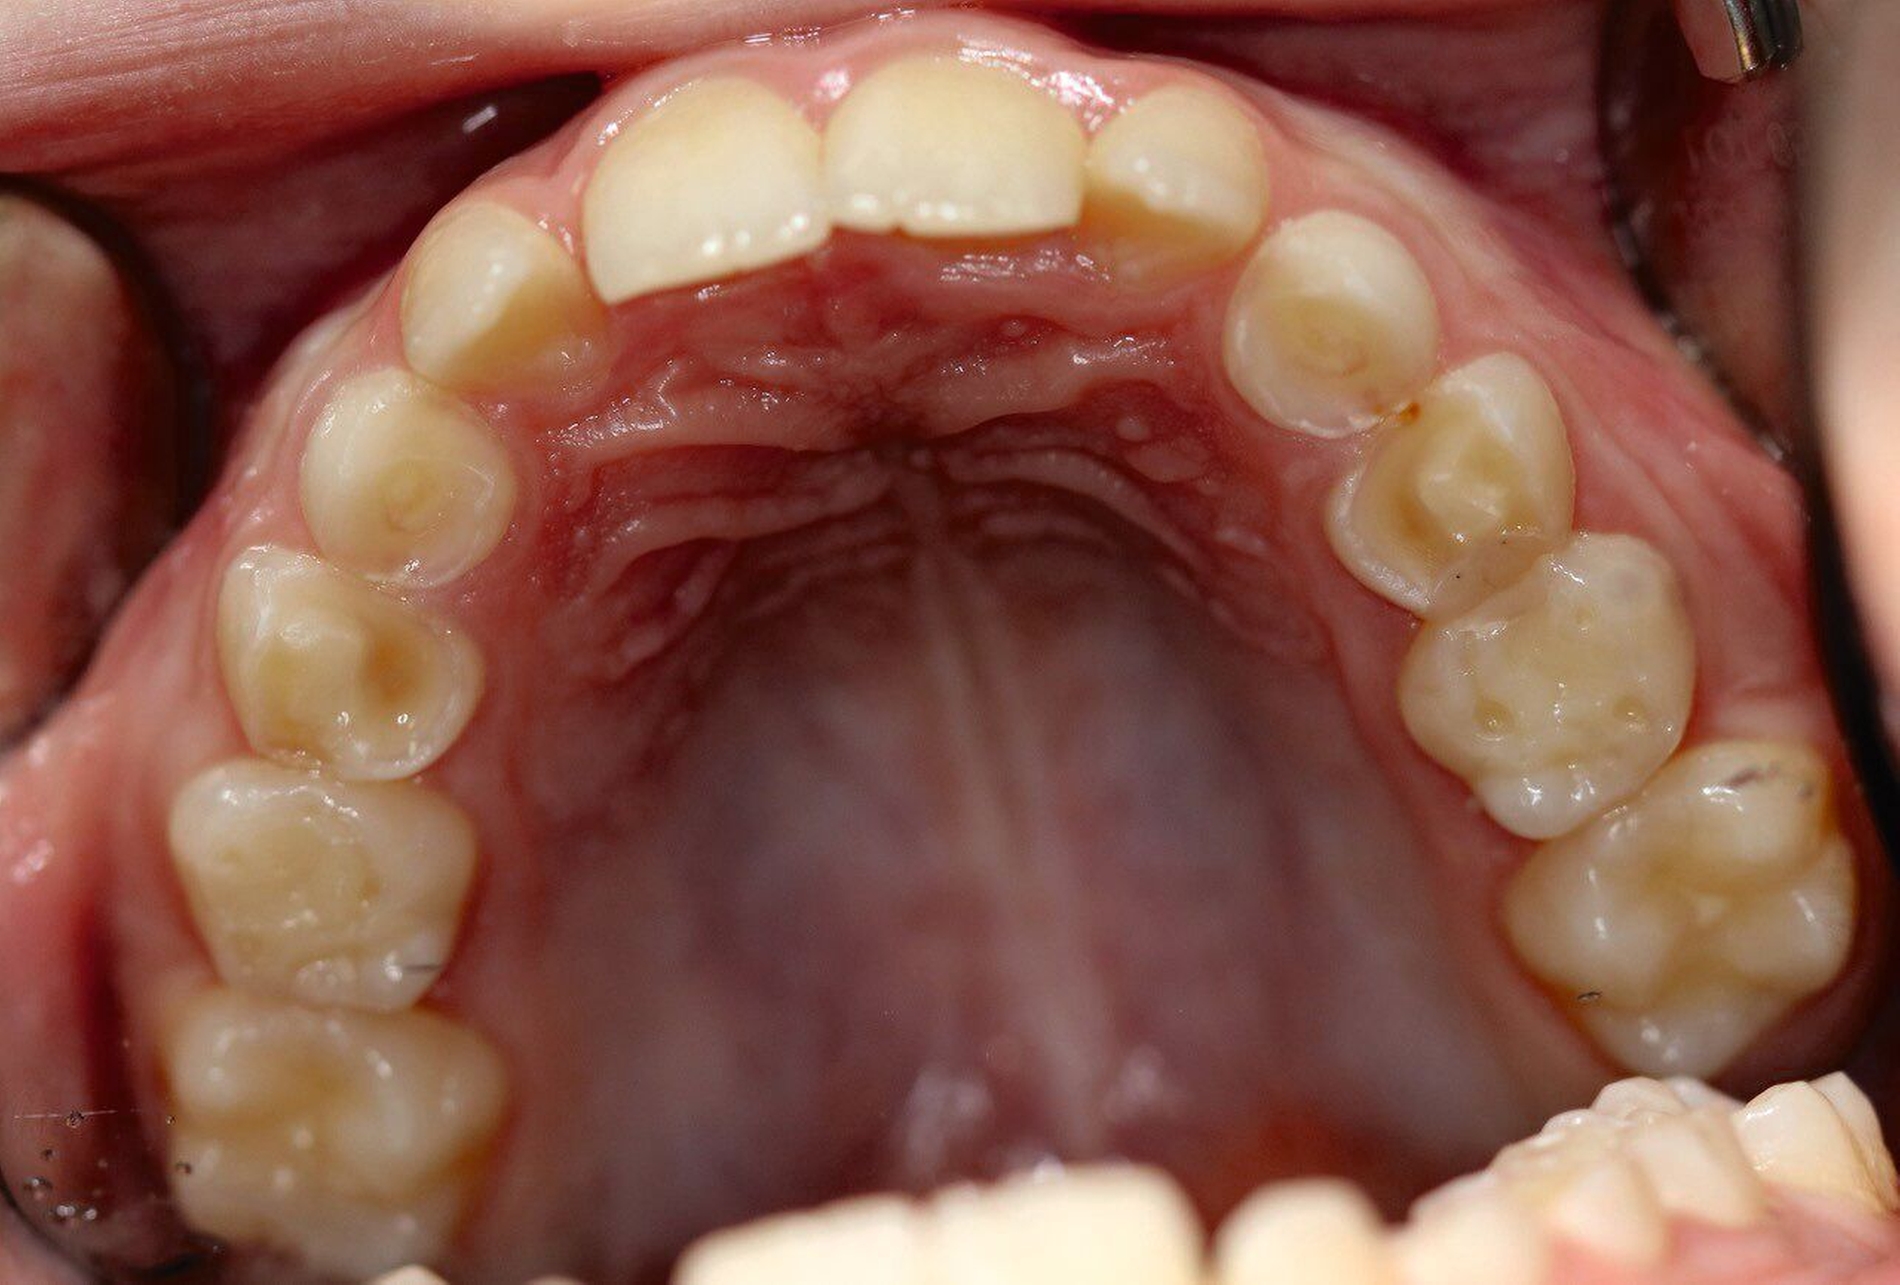

Glänzende Facetten, eine gleichmäßige Abnutzung der Schmelz-und Dentinflächen und das „Schlüssel-Schloss-Prinzip“ werden meist durch Attrition verursacht. Auch Abdrücke in den Weichgeweben wie Lippe und Wange beziehungsweise Frakturen an bestehenden Restaurationen der Antagonisten sind charakteristische Merkmale. Abrasionen hingegen werden extrinsisch durch Fremdkörper verursacht, wohingegen Erosionen auf die Einwirkung von Säuren zurückgehen. Säuren lösen Mineralien aus dem Zahnschmelz heraus. Dadurch kann Zahnhartsubstanz abgetragen werden. Typisch sind sogenannte okklusale Rillen, Abrundungen von Höckern und Auswaschungen (Abbildungen 1 und 2). Typisch ist hier auch der Zahnhartsubstanzverlust an Flächen, die normalerweise nicht okkludieren. Restaurationen zeigen sich erhaben und Amalgam erscheint glänzend [Wetselaar und Lobbezoo, 2016].

Eine präzise Zuordnung der Art des Zahnhartsubstanzverlusts ist häufig schwierig und nicht immer eindeutig möglich, da viele Patienten Mischformen aufweisen. Das „Schlüssel-Schloss-Prinzip“ ist aber das sicherste Diagnosekriterium für Bruxismus. Zur besseren Übersicht sind in Tabelle 1 die Merkmale von Erosionen, Attritionen und Abrasionen aufgelistet.